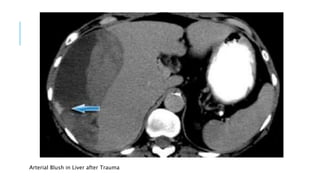

Arterial Blush in Liver after Trauma

Arterial Blush inLiver after Trauma